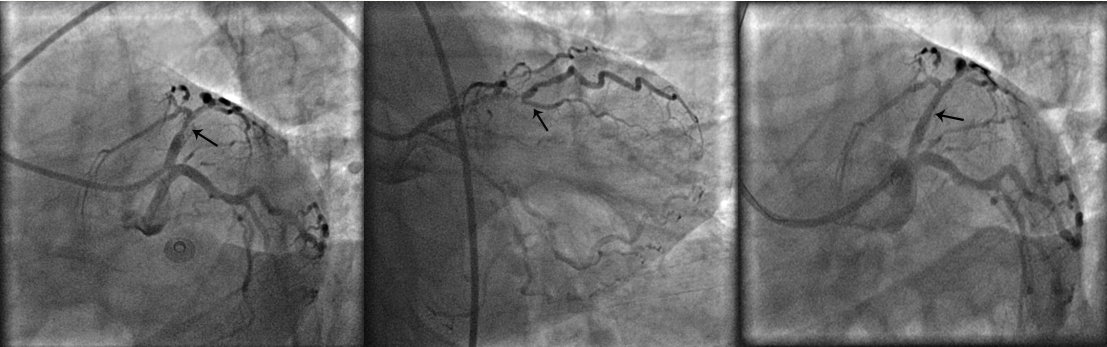

Abstract PDF ECG 1 Angio 1 Angio 2 Angio 3 Angio 4 ECG 2 Table Chart Original File 1 2 3 4 5 6 Reply to reviewer Fig. 1. ECG during myocardial infarction Fig. 2. Coronary angiography of LCA during myocardial infarction Fig. 3. Coronary angiography of LCA during myocardial infarction Fig. 3a. Coronary angiography of LCA during myocardial infarction Fig. 4. Coronary angiography of LCA 2 years after myocardial infarction Fig. 5. Coronary angiography of LCA 2 years after myocardial infarction Fig. 6. ECG 2 years after myocardial infarction Fig. 7. Thrombolytic trials in patients with coronary artery dissection Fig. 8. Flow chart of the study selection process -

Abstract Figure 1 Bez naslova Bez naslova Bez naslova Bez naslova Bez naslova 1 2 3 4 5 -